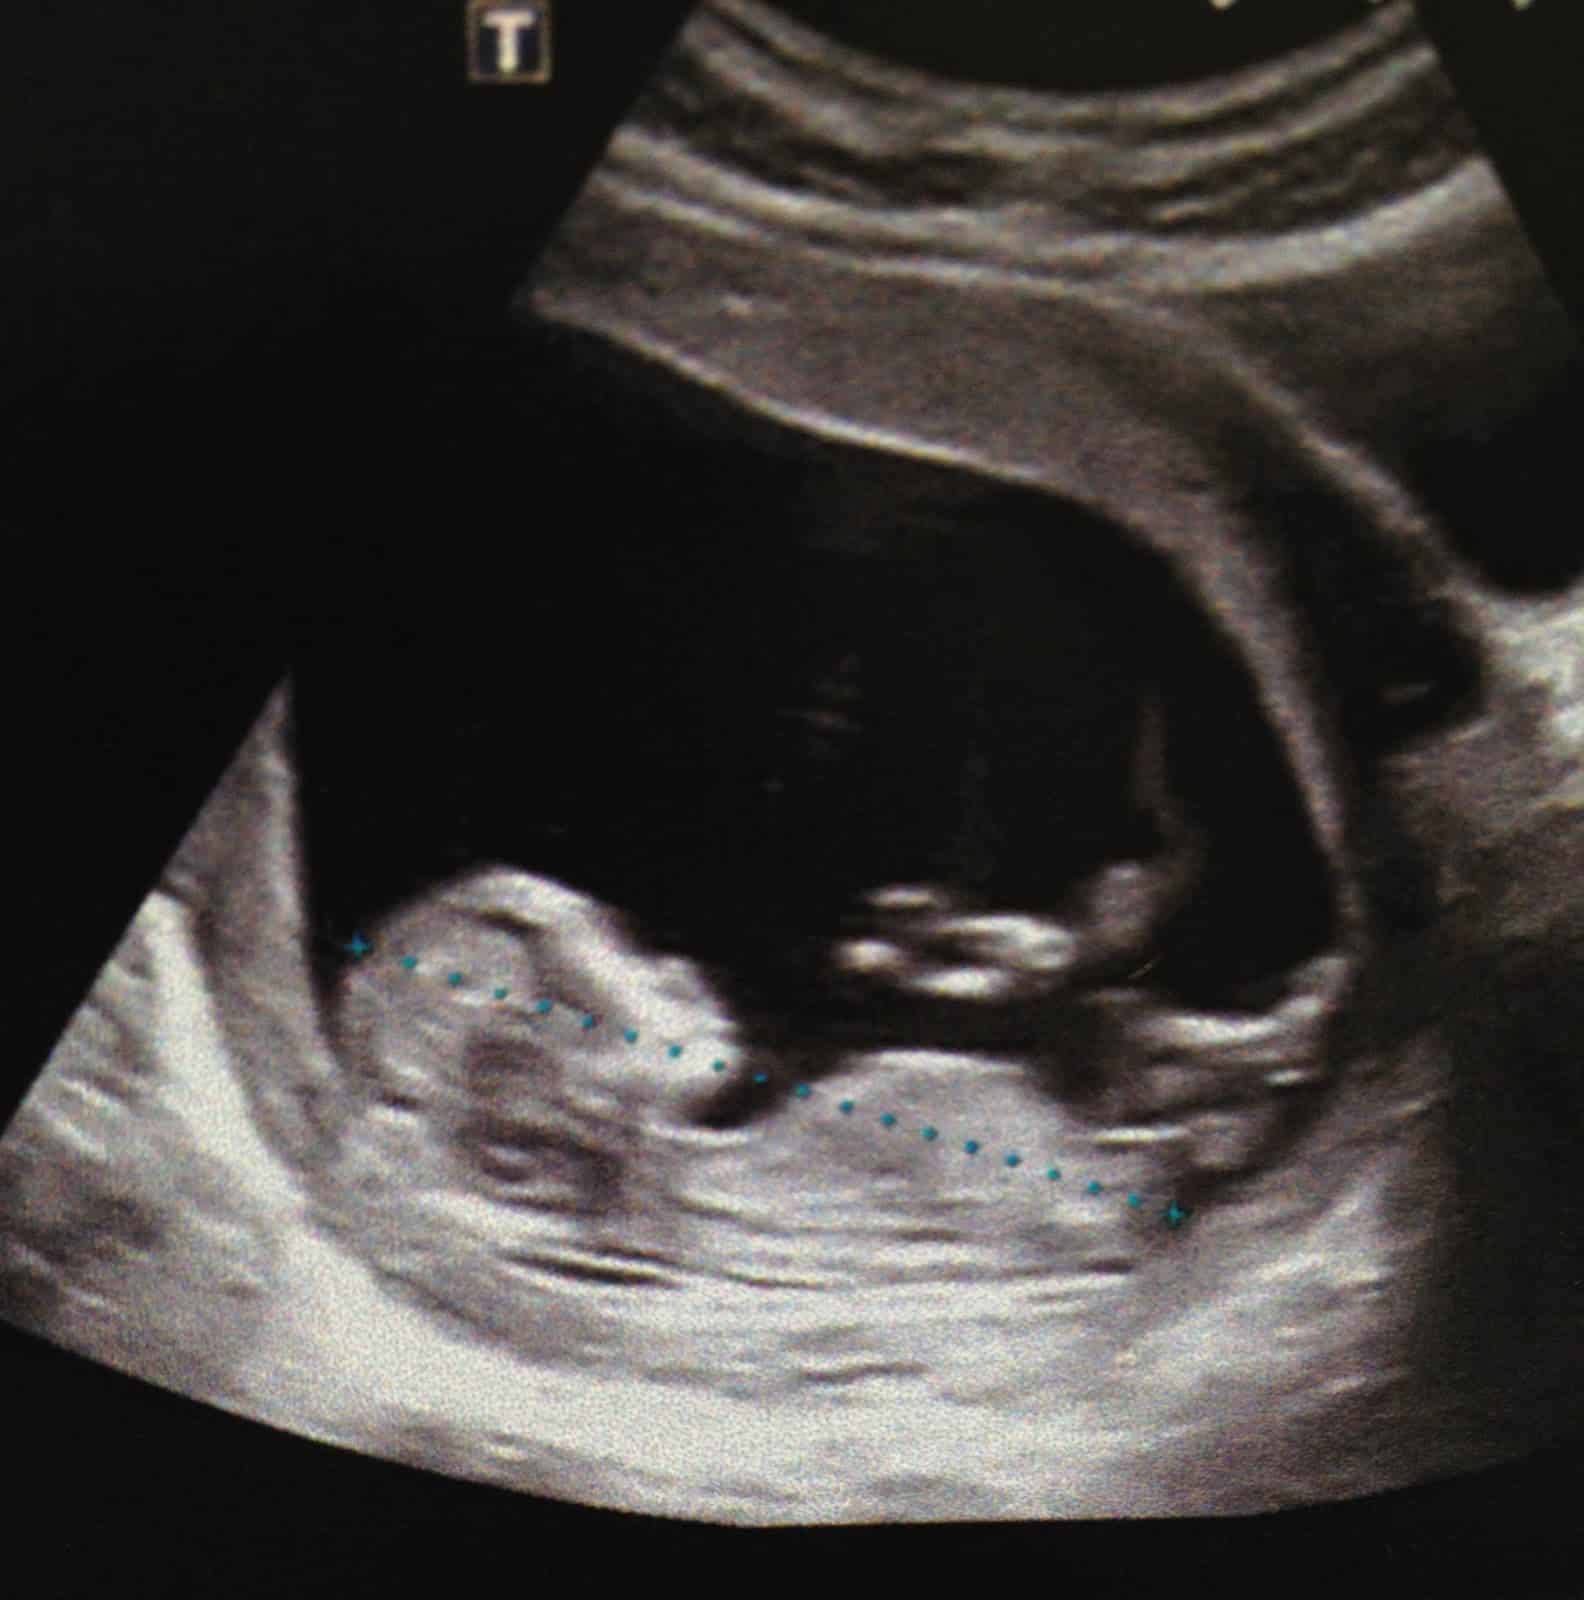

Je lui ai expliqué pourquoi j’étais là, l’écho des 12 semaines, il a pris 5 minutes, pour faire l’écho gratuitement, pour me montrer ce que je n’avais pas vu. Et j’ai vu un bébé et même en 3 D.

C’est impressionnant.

Un bébé qui dort la tête appuyée sur ses bras comme s’il dormait dans l’herbe et qu’il regardait les nuages. Un bébé peace.